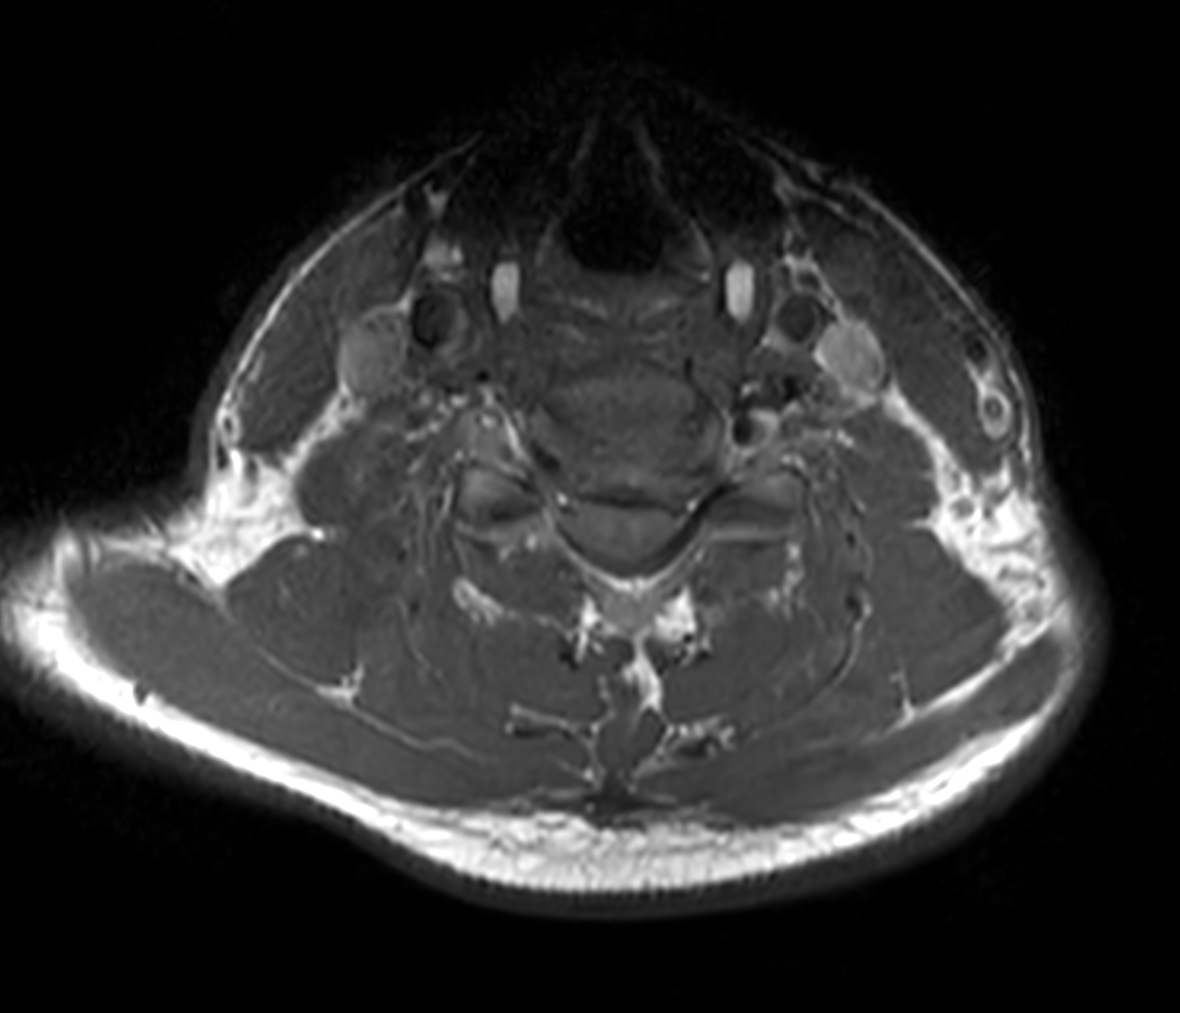

Axial T2w TSE

Axial T2w TSE - Compressed SENSE